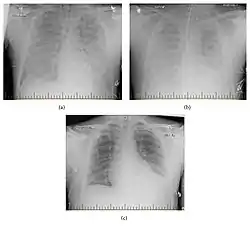

![]() صورةُ أشعة تظهر التطور الرئوي الحاصل في متلازمة فيروس هانتا. تُمثل (a) الصورة عن ظهور الأعراض لأول مرة، (b) صورة في اليوم الثاني من الدخول إلى المستشفى وبعد الأكسجة الغشائية خارج الجسم، (c) صورة في اليوم العاشر من الدخول إلى المستشفى وذلك بعد تركيب أنبوبٍ للشخص صورةُ أشعة تظهر التطور الرئوي الحاصل في متلازمة فيروس هانتا. تُمثل (a) الصورة عن ظهور الأعراض لأول مرة، (b) صورة في اليوم الثاني من الدخول إلى المستشفى وبعد الأكسجة الغشائية خارج الجسم، (c) صورة في اليوم العاشر من الدخول إلى المستشفى وذلك بعد تركيب أنبوبٍ للشخص | |